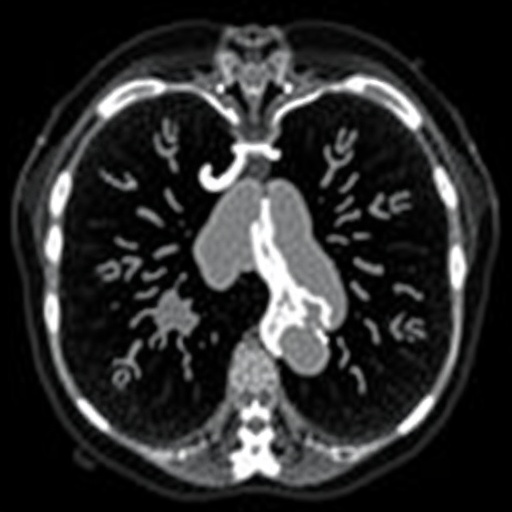

Hydrocephalus, often a congenital anomaly, can also develop secondary to infections, tumors, or traumatic injuries. In the emergency department, the urgent need for accurate and rapid diagnosis is paramount. Given the array of potential underlying causes and the serious implications of delayed treatment, practitioners must rely heavily on advanced imaging techniques. The recent study emphasizes the vital role of modalities such as ultrasound, computed tomography (CT), and magnetic resonance imaging (MRI) in effectively assessing ventriculomegaly.

Computed tomography offers a quick yet potent alternative, especially when a more detailed assessment is required in older infants and children. The ability to analyze bony structures, detect incidental findings, and provide rapid triage capabilities makes CT an indispensable tool in emergency settings. However, the inherent risks associated with radiation exposure in pediatric populations remain a consideration, urging clinicians to weigh the risks and benefits carefully.

Against this backdrop, magnetic resonance imaging emerges as the gold standard for evaluating pediatric hydrocephalus. MRI provides unparalleled detail in visualizing brain anatomy and pathology. The use of contrast agents further enhances the modifiable capacity to delineate between various etiologies of ventriculomegaly and other complications, such as impaired aqueductal flow. However, accessibility issues and the longer duration of MRIs compared to CTs can present logistical challenges in emergency scenarios.